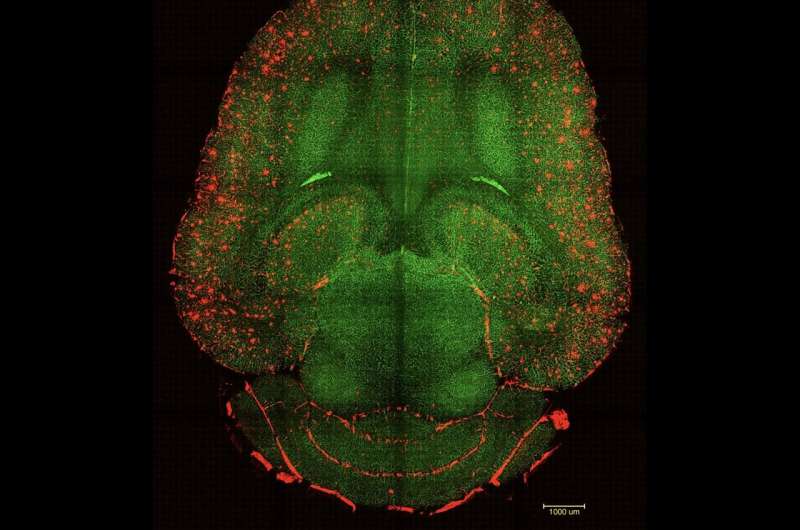

3D xəritələr siçan beyninin əlaqəsini formalaşdıran gizli mikromühitləri aşkar edir

İnqrid Fadelli , Medical Xpress tərəfindən Stephanie Baum tərəfindən redaktə edilib , Robert Egan tərəfindən nəzərdən keçirilib  Redaktorların qeydləriKomandanın məqaləsində təqdim olunan əsas ideyaları ümumiləşdirən